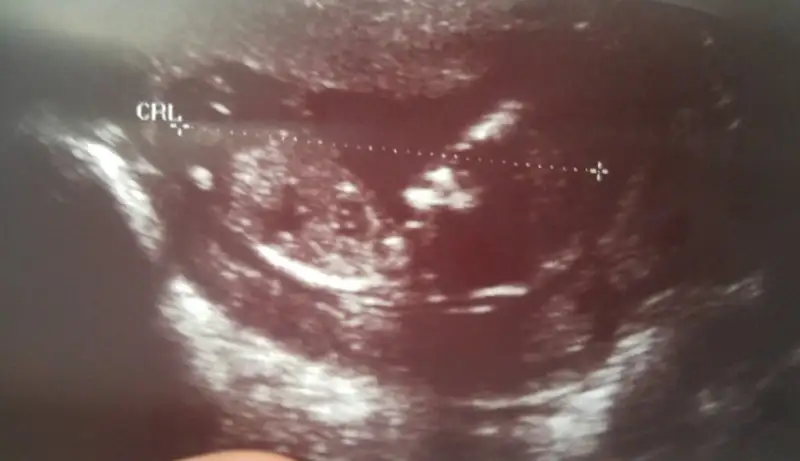

Kızlar bugün özele doktora gittim ense kalınlığı olculsun diye hemde belki cinsiyet ogreniriz diye minik bir erkek geliyormuş ❤❤ bir kızım vardi Rabbim nasip ederse birde oğlum olacak❤

Ense kalinligide 1.2 ölçtü bu doktor ama haftaya bi daha gel yine bakalim dedi